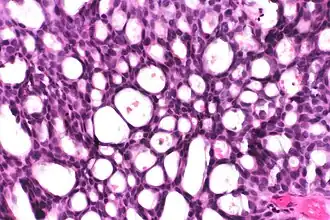

This can be done to slides processed by the chemical fixation or frozen section slides. To see the tissue under a microscope, the sections are stained with one or more pigments. The aim of staining is to reveal cellular components; counterstains are used to provide contrast.

The most commonly used stain in histology is a combination of hematoxylin and eosin (often abbreviated H&E). Hematoxylin is used to stain nuclei blue, while eosin stains the cytoplasm and the extracellular connective tissue matrix of most cells pink. There are hundreds of various other techniques which have been used to selectively stain cells. Other compounds used to color tissue sections include safranin, Oil Red O, congo red, silver salts and artificial dyes. Histochemistry refers to the science of using chemical reactions between laboratory chemicals and components within tissue. A commonly performed histochemical technique is the Perls' Prussian blue reaction, used to demonstrate iron deposits in diseases like Hemochromatosis.[2]

Recently, antibodies have been used to stain particular proteins, lipids and carbohydrates. Called immunohistochemistry, this technique has greatly increased the ability to specifically identify categories of cells under a microscope. Other advanced techniques include in situ hybridization to identify specific DNA or RNA molecules. These antibody staining methods often require the use of frozen section histology. These procedures above are also carried out in the laboratory under scrutiny and precision by a trained specialist medical laboratory scientist (a histoscientist). Digital cameras are increasingly used to capture histopathological images.